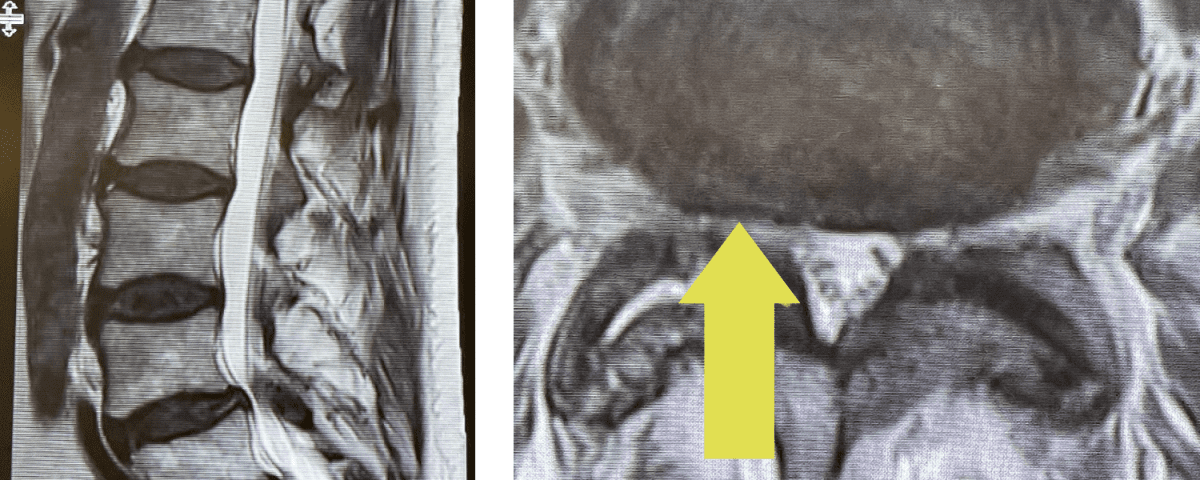

Fig 1: Sagittal and axial T2-weighted lumbar MRI demonstrating severe L4-5 Stenosis and grade 1 spondylolisthesis. Note (yellow arrow) cystic anteromedial extension off the right facet joint causing right-sided lateral recess cut-off of thecal sac and compression of the right L5 nerve root.

This 70 year-old male with two years of right leg pain with minimal low back pain. The patient had tried physical therapy and epidural injections. Neurologically he was intact. MRI revealed a grade 1 spondylolisthesis (slipped spine in Greek) at L4-5 with severe lumbar stenosis mainly due to thickened yellow ligament and overgrown joints; but the thing that I believe put him over the edge was a small joint cyst on the right (Fig 1). People just form cysts. You can get a cyst in practically every organ including kidney, liver, ovarian, etc. People are actually fascinated by them. When patients have spine surgery the only thing that matters to them is, “did you get the cyst?” The fact is that they are these small gelatinous balls that come off the joint space and grow into the spinal canal and cause symptoms by compressing the nerve. You essentially bite them away with our instruments. You really can’t aspirate them through the skin. They are just a form of arthritis and are always benign.